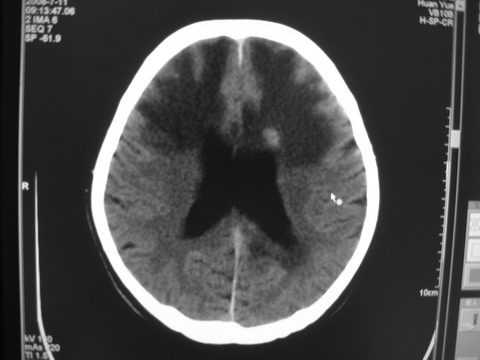

患者 男 69岁 头晕头痛不适

多发病灶,指状水肿,首先诊断转移瘤。

多个结节并周围大面积水肿区,多考虑多发性脑转移瘤

小病灶、大水肿,病灶多发,首先考虑多发转移瘤;建议查原发灶。

额顶叶多发小病灶、大水肿,首先考虑多发转移瘤;建议查原发灶

脑内多发病灶,小病灶,大水肿。

典型转移性肿瘤。

应进一步检查,查找原发病灶。

结果 : 该患者结肠癌病史5年 考虑脑转移